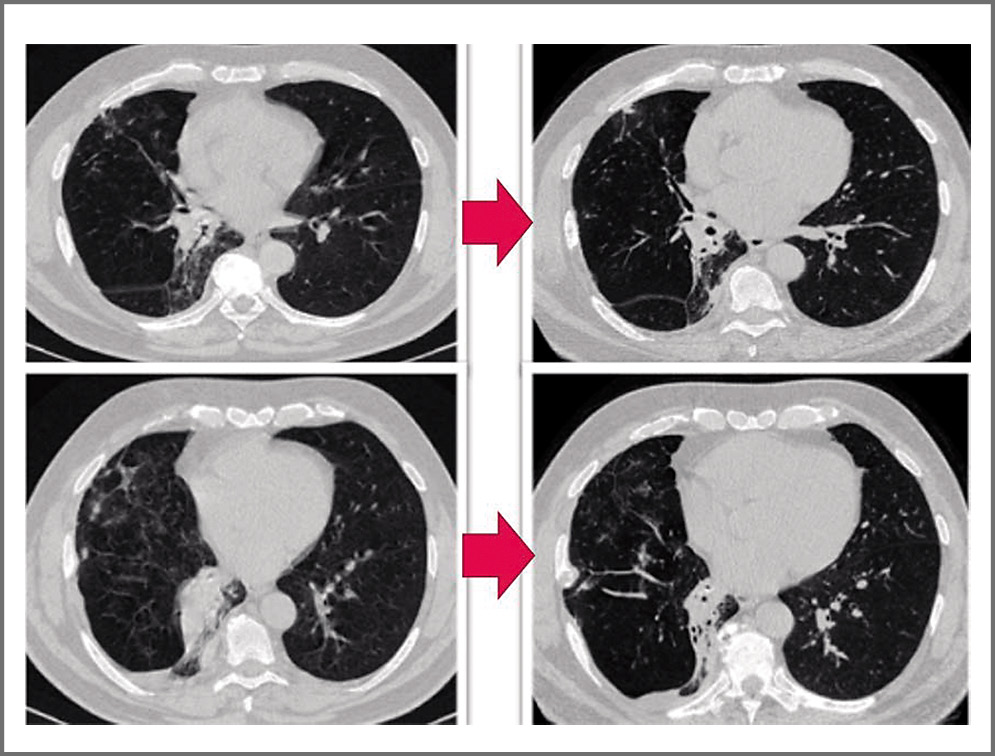

При применении противогрибкового препарата у пациента отмечена положительная клинико-рентгенологическая динамика в виде уменьшения приступообразного кашля с трудноотделяемой мокротой, частичное рассасывание зон консолидации легочной ткани в нижней доле правого легкого при контрольной КТ ОГК от 30.08.2020 (рис. 3).

Рис. 3. КТ-динамика пациента П. за 2 мес противогрибковой терапии (от 03.06.2020 к 30.08.2020 слева направо), отмечено частичное рассасывание зон консолидации легочной ткани в правом легком, стали видны просветы бронхов.

Fig. 3. CT dynamics of patient P. for 2 months of antifungal therapy (from 03.06.2020 to 30.08.2020 from left to right), there was a partial resorption of the consolidation zones of the lung tissue in the right lung; the lumens of the bronchi became visible.

С учетом нивелирования значительной части инфильтративных изменений в зоне поражения и подозрения на наличие инородного тела совместно с заведующим отделением эндоскопии принято решение о выполнении повторной бронхоскопии с целью эвакуации обтуратора. 25.09.2020 пациенту выполнена бронхоскопия под наркозом, при которой отмечено уменьшение зоны пролиферативных изменений слизистой ТБД справа, достигнута визуализация инородного тела белого цвета и выполнена его криоэкстракция из промежуточного бронха (рис. 4, i–h).